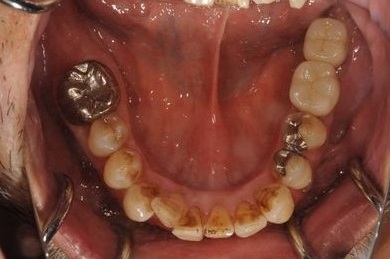

| 性別/年齢 | 男性 / 60歳 | ||||||||||||||||||||||||||||||||

| 主訴 | 右下奥歯の治療相談。(痛み・ぐらつき・物がかめない) | ||||||||||||||||||||||||||||||||

| 治療方針 | 左下奥の欠損部分をインプラント治療にて、機能的・審美的に回復を行う。 | ||||||||||||||||||||||||||||||||

| 治療内容 | インプラント2本、メタルボンドセラミッククラウン2本 | ||||||||||||||||||||||||||||||||

| 総治療費 | 680,610円 | ||||||||||||||||||||||||||||||||

| 治療期間 | 7ヶ月 |